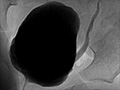

A voiding cystourethrogram (say "sis-toh-you-REE-throh-gram") is a test that is done to see if there are problems with the urinary system and to see how urine flows out of the bladder. This test, also called a VCUG, uses contrast fluid and X-rays so the doctor can see how the bladder fills and drains.

The bladder appears normal.

Urine flows normally from the bladder.

The bladder empties all the way.

The contrast material flows evenly out of the bladder through a smooth-walled urethra.